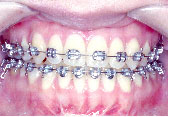

術前矯正がうまくいったので術後矯正は微調整で済みました。

骨が固まり安定するまで待って装置をはずします。

あごのずれもなくなり、バランスのとれた美しい口元になりました。咬み合わせも非常に良くなってご本人は大変満足されています。

治療期間は3年7か月です。